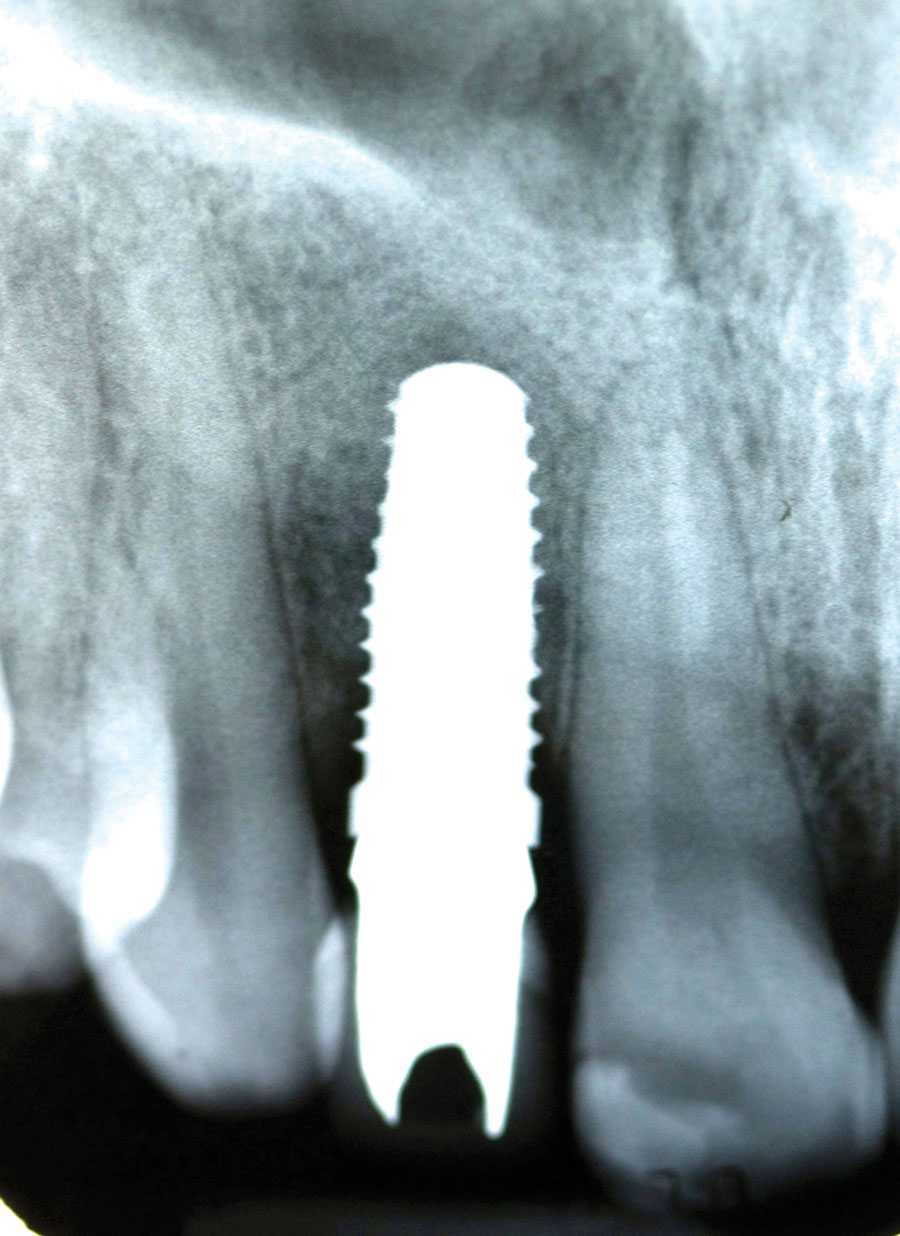

Add a description…5×13 3i alternate text for this image

Achieving ideal esthetics in addition to restoring the patient’s function is every clinician’s goal. Successful outcomes in restorative dentistry are well documented in publications and readily displayed in practice promotional materials. Although most patients are happy with the treatment outcomes, achieving highly esthetic result can be challenging in implant dentistry. Successful implant integration does not … Read more